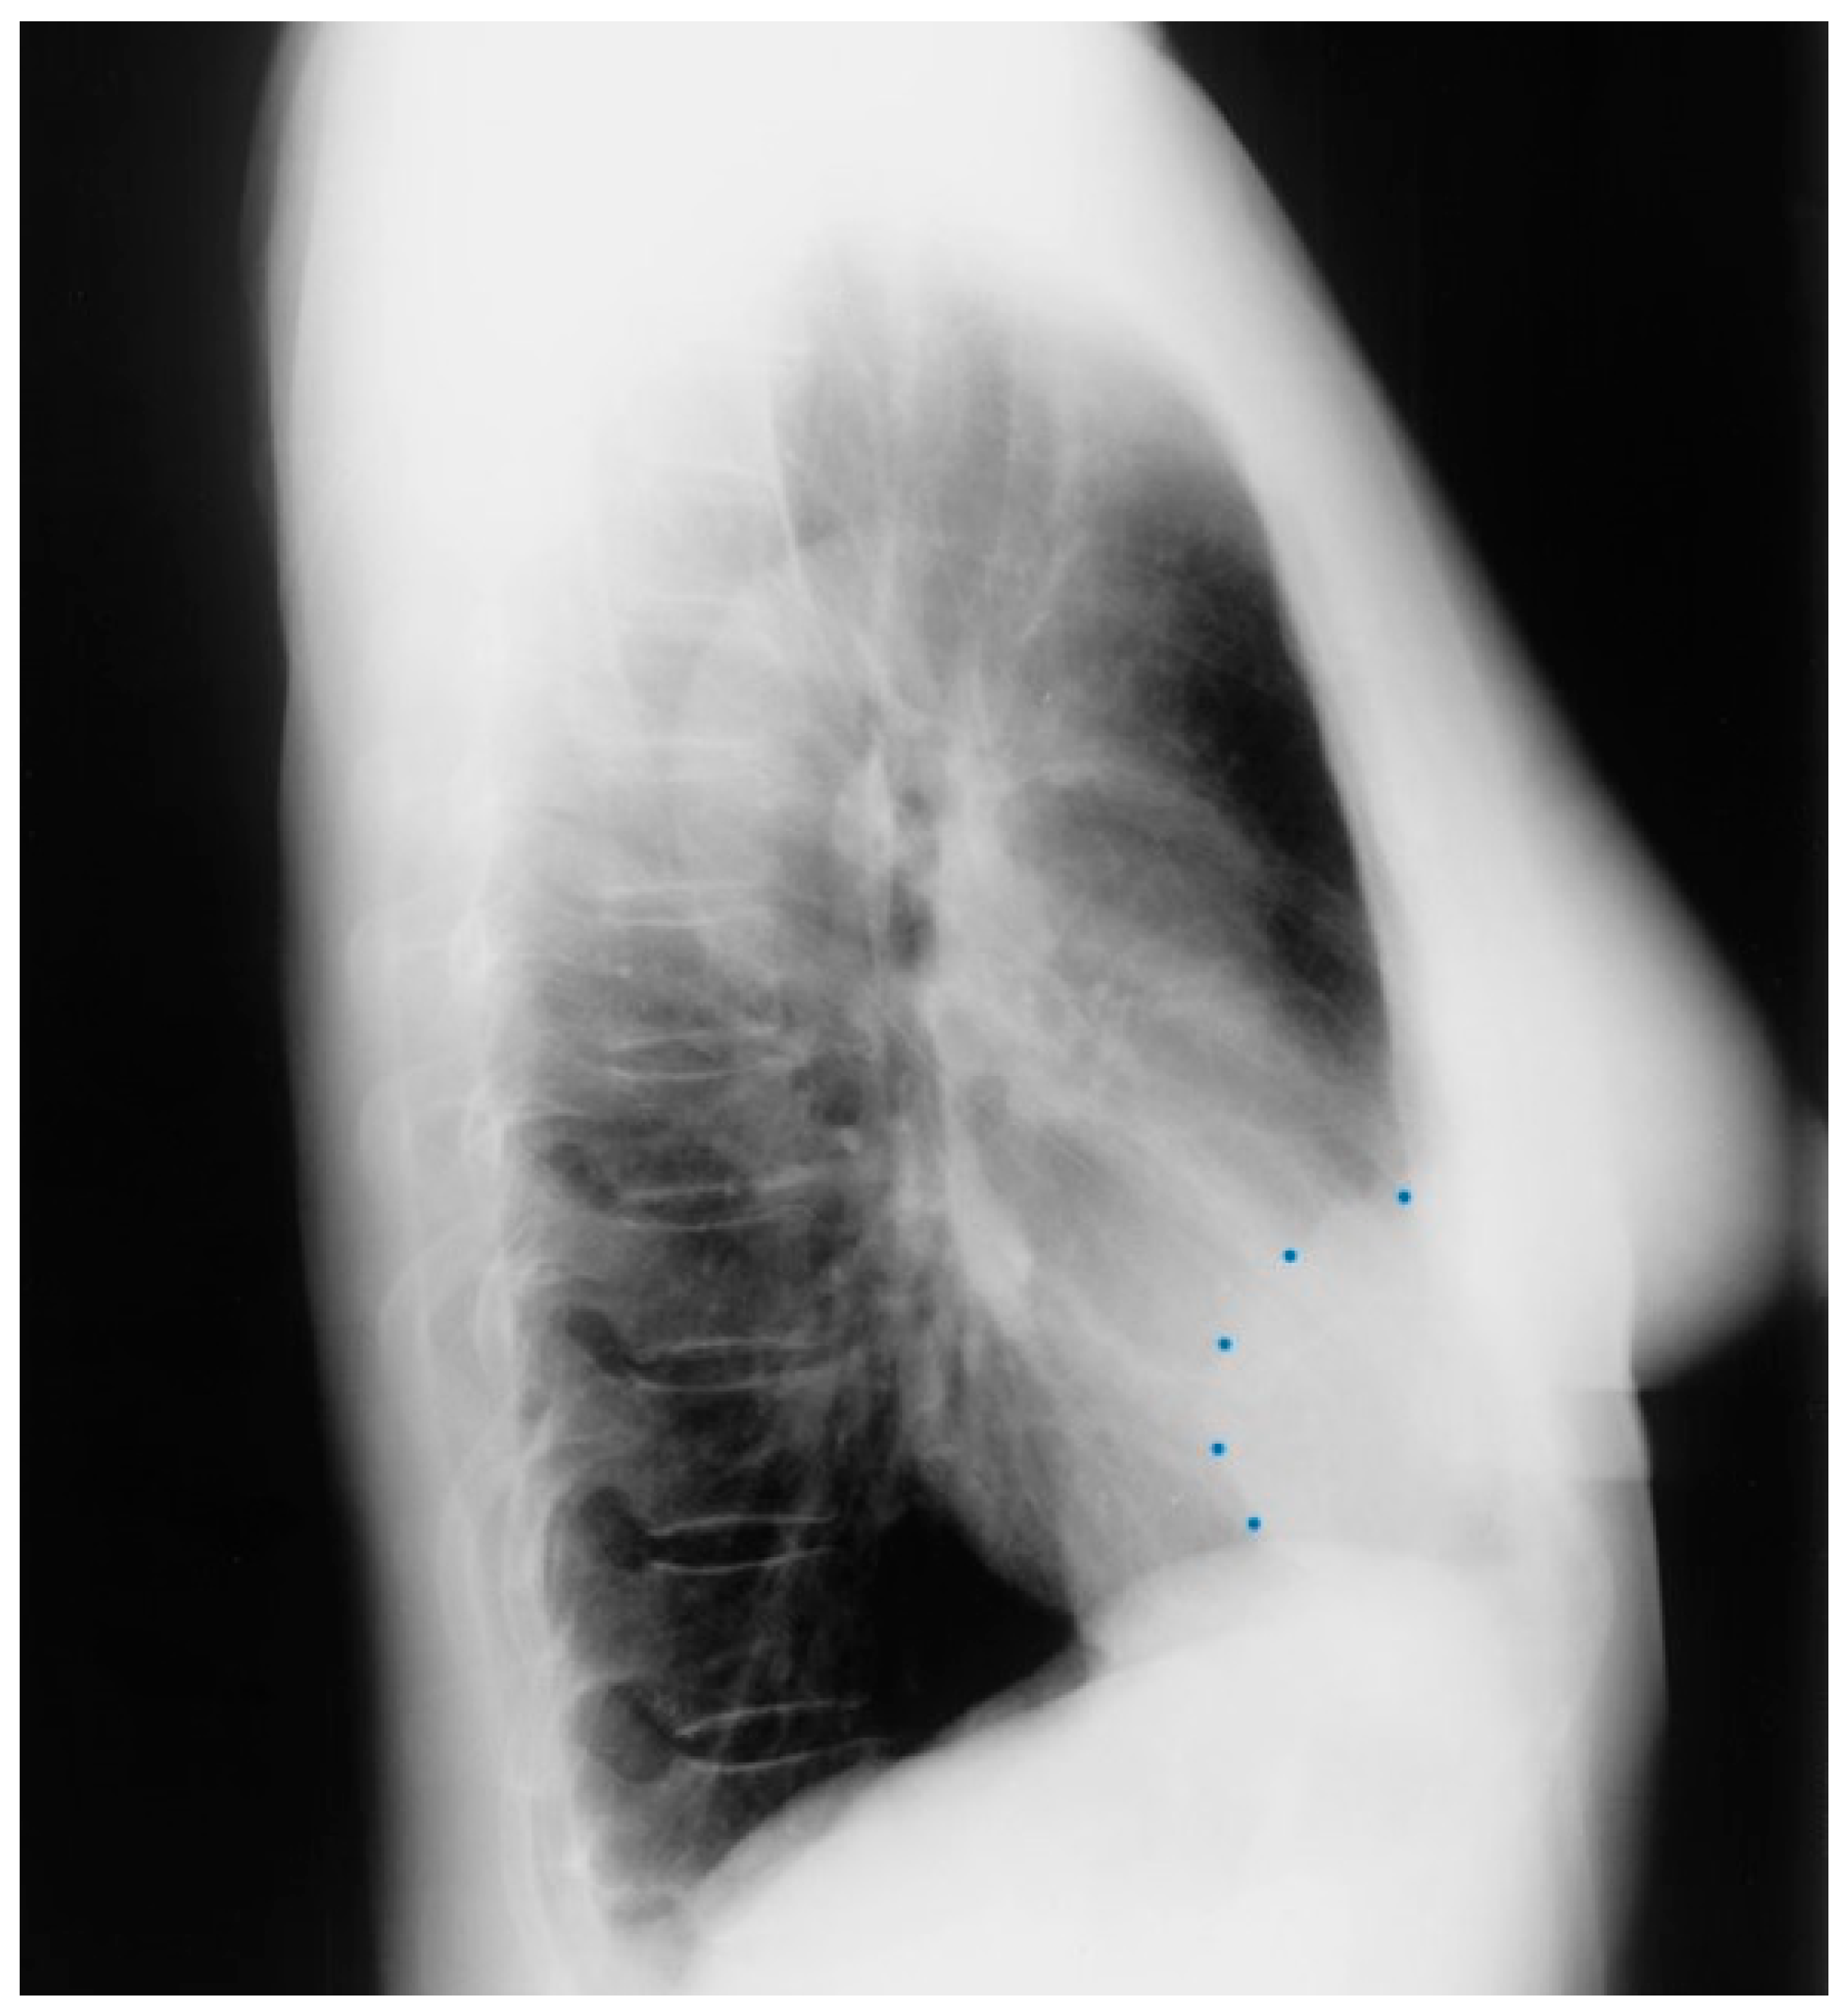

Figure 3.

Lateral chest X-ray of a pericardial cyst: This is the lateral chest X-ray of the same-40 year-old female with a right cardiophrenic angle pericardial cyst. This image demonstrates that this pericardial cyst (blue dots) is located anteriorly in the chest and adjacent to the heart, and explains the silhouette sign on the posteroanterior chest X-ray. In this image, because the cyst and the heart are superimposed, their radiodensities are summed and the cyst appears denser than the rest of the heart that it does not overlie.